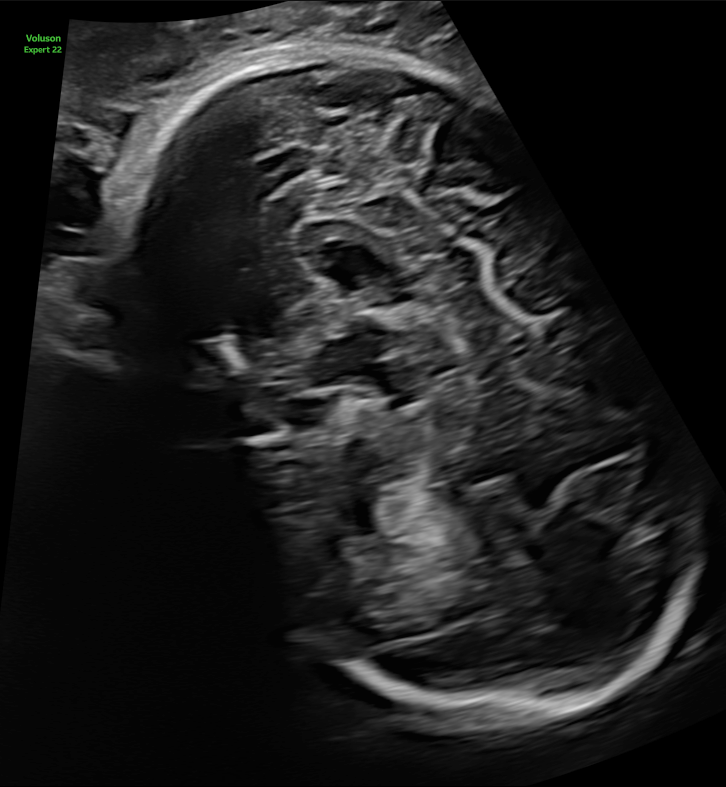

Voluson Expert 22では、より膨大な情報を高速処理可能な次世代エンジンLyric Architectureを搭載したことで、ソフトウェア制御されたビームフォーミングを実現。ハードウェア制御の限界を超え、格段に向上したペネトレーション、分解能、フレームレートを提供します。また、従来のVoluson製品では活用できなかった、新たなレベルの画像処理が可能となり、分解能に特化したイメージングモードから、深部感度に特化したイメージングモードまで、観察条件に大きく左右されることのない、明瞭な画像を提供します。

分解能に特化したイメージングモード:UltraHD with Radiant